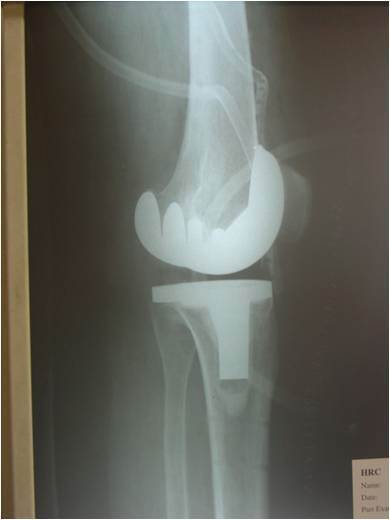

Postoperative plain X-ray showing the super stablized implant